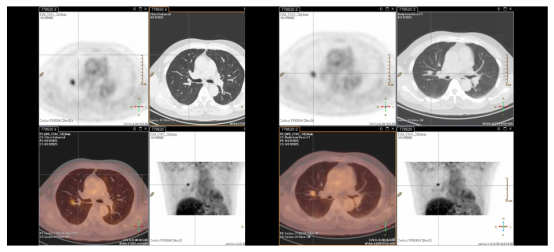

2022.07胸腹部CT:右肺下叶见片状实变影;肝左外叶上段结节,考虑左肝新发转移瘤。

2022.08PET-CT见肝左外叶糖代谢增高,SUV值为10.8。粒子植入术后膈肌上方局限性放射性肺损伤,自行好转。

image.png

图8 影像评估提示肝左外叶糖代谢增高